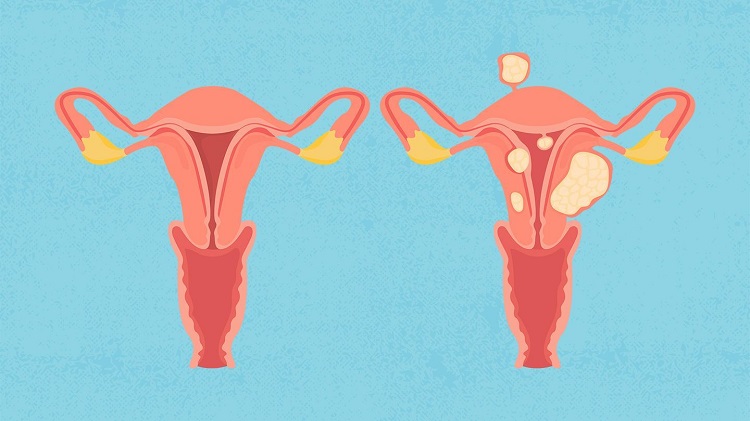

فیبرومهای رحمی از شایعترین تومورهای خوشخیم در زنان در سن باروری هستند که میتوانند باعث علائم ناخوشایندی مانند خونریزیهای شدید قاعدگی، درد لگن و مشکلات باروری شوند. در حالی که درمانهای پزشکی و جراحی برای فیبروم وجود دارد، اخیراً توجه به مداخلات غیرتهاجمی مانند ورزش به عنوان یک روش مکمل افزایش یافته است. این مقاله به بررسی نقش ورزش در مدیریت فیبرومهای رحمی، مکانیسمهای اثرگذاری و بهترین انواع فعالیتهای ورزشی برای این منظور میپردازد.

نشان داده شده که ورزش، سطح استروژن و پروژسترون را کاهش میدهد. ورزش منظم ممکن است با کاهش هورمونها و فیبرومها که اغلب توسط هورمونها تحریک میشوند، از رشد فیبرومها جلوگیری کند. مطالعات همچنین نشان میدهد که شاخص توده بدنی (BMI) بالاتر با رشد فیبروم مرتبط است. ورزش منظم در کاهش BMI تاثیر دارد، بنابراین میتواند رشد فیبروم را نیز کاهش دهد.

در حالی که ورزش ممکن است به جلوگیری از رشد فیبروم رحم کمک کند، اما برای کنترل یا کاهش اندازه (یا علائم) فیبرومهایی که دارید، کمک زیادی نمیکند. با این حال، یک راه بسیار کارآمد، کوچک کردن فیبرومها به اندازهای است که علائم ایجاد نکنند.

آمبولیزاسیون فیبروم نیز با محروم کردن فیبرومها از خونرسانی، آنها را کوچک میکند. بدون مواد مغذی و اکسیژن در خون، فیبرومها گرسنگی میکشند. آمبولیزاسیون یک درمان غیرجراحی است که فیبروم و علائم فیبروم را بدون نیاز به جراحی کاهش میدهد. فیبرومهایی که به درستی آمبولیزه شدهاند هرگز دوباره ظاهر نمیشوند و دوباره رشد نمیکنند.